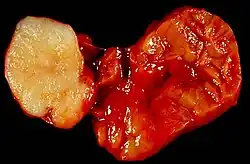

Benign tumour of the submandibular gland, also known as pleomorphic adenoma, presented as a painless neck mass in a 40-year-old man. At the left of the image is the white tumour with its characteristic cartilaginous cut surface. To the right is the normally lobated submandibular salivary gland.Warthin's tumor

Specimen from a parotid gland tumour. It was removed by John Hunter from a 37-year-old man named John Burley on 24 October 1785. The tumour weighed over 4 kilograms and took twenty-five minutes to remove. The specimen currently resides in the Hunterian Museum at the Royal College of Surgeons of England.